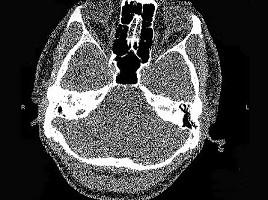

问题 男,23岁,右耳流脓十余年,右外耳道流脓,鼓膜穿孔,CT检查如图,最可能诊断为 ( )

选项 A、嗜酸性肉芽肿 B、(海绵化期)耳硬化症 C、中耳乳突结核 D、中耳癌 E、慢性中耳乳突炎

答案 E